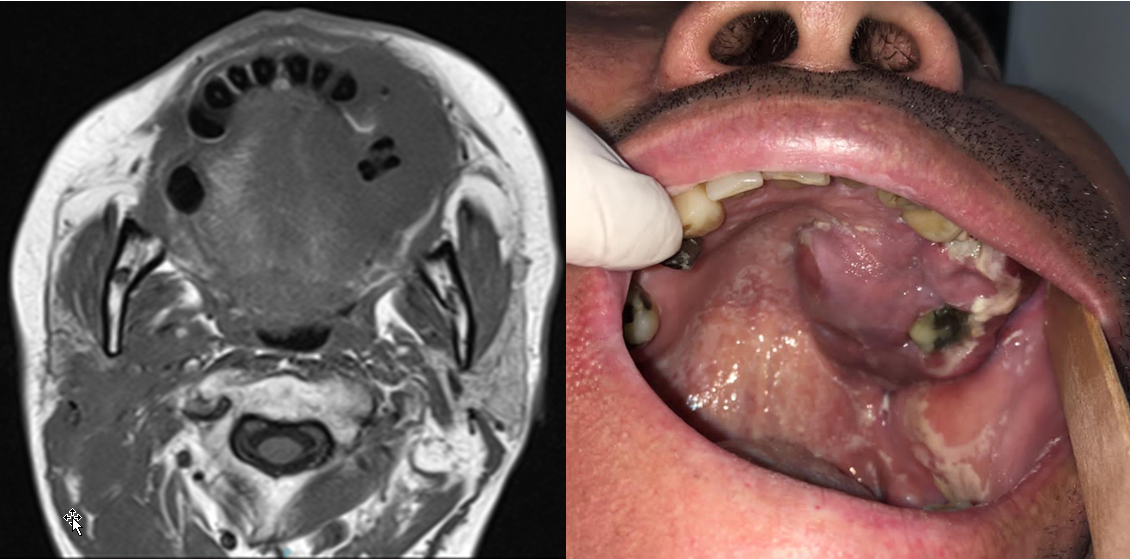

Recaída de linfoma de Burkitt en paladar